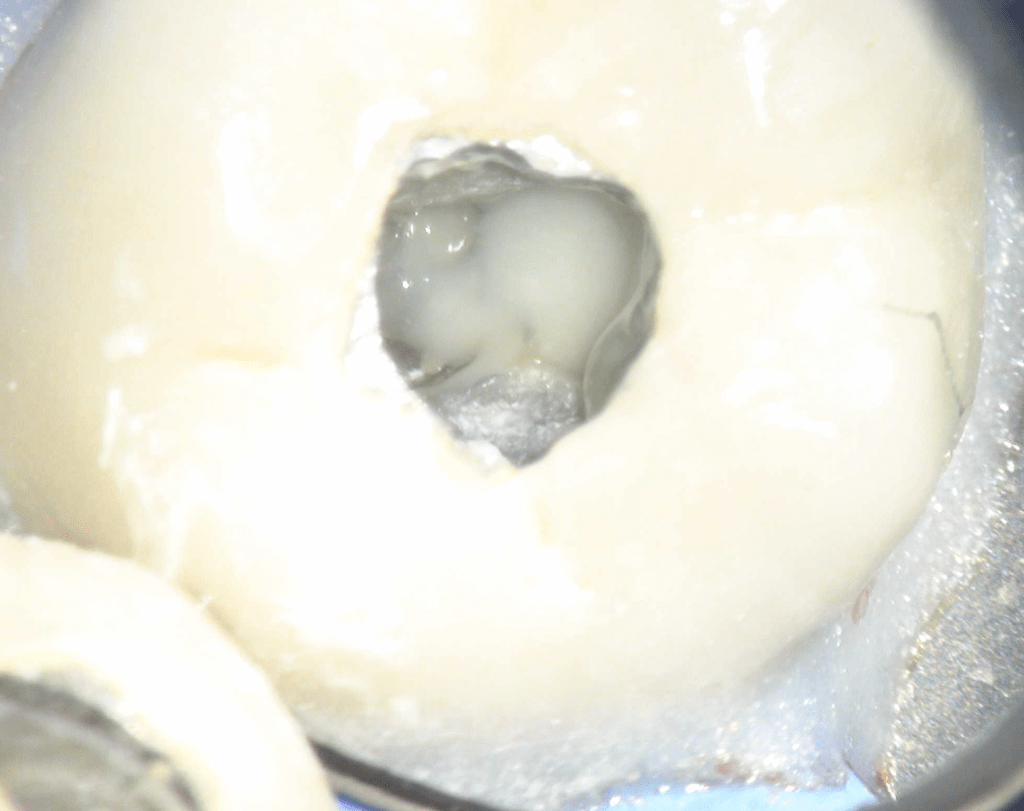

Fisura, remoción amalgama para explorar